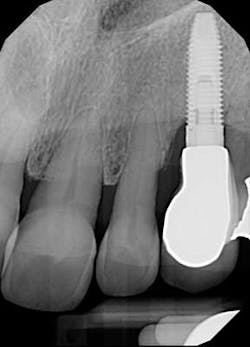

I choose to keep the abutment and crown, seat them correctly, cement the crown with a retrievable cement, and monitor the patient in two weeks. After seating the abutment fully, I seat the crown and take a radiograph for confirmation.

Fig. 6: Periapical radiograph after correct seating of components.